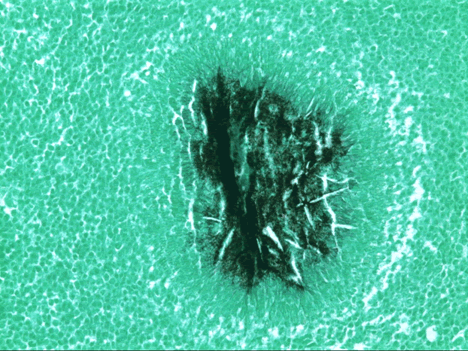

A Tru-cut needle biopsy was performed at bedside which revealed nonspecific pathologic findings, but a repeat with increased sampling revealed acute and chronic inflammation with granulation tissue containing Actinomyces confirmed by periodic acid shift (PAS), Gomori’s methamine silver (GMS), and modified Gram stains (Figure 3). Treatment began with intravenous Penicillin G (4 million units every 4 hours for a 6 week course) which will be followed by oral amoxicillin for 6-12 months. A repeat CT scan was planned in 4 weeks, as actinomycosis is known to colonize malignant tissue. The patient, at three month follow up, was doing well from a pulmonary standpoint and had regression of his chest wall mass.